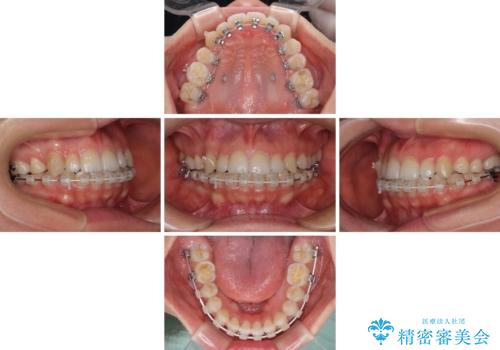

- ハーフリンガル

目立たない装置を希望されたので、上顎が裏側装置のハーフリンガルを選択し、上顎小臼歯1本を抜歯して、補助装置を併用して矯正治療を行うこととしました。

補助装置を事前に使用したことで、あっという間に八重歯が改善し、ハーフリンガルにしては1年半もかからずに治療を終えることができました。